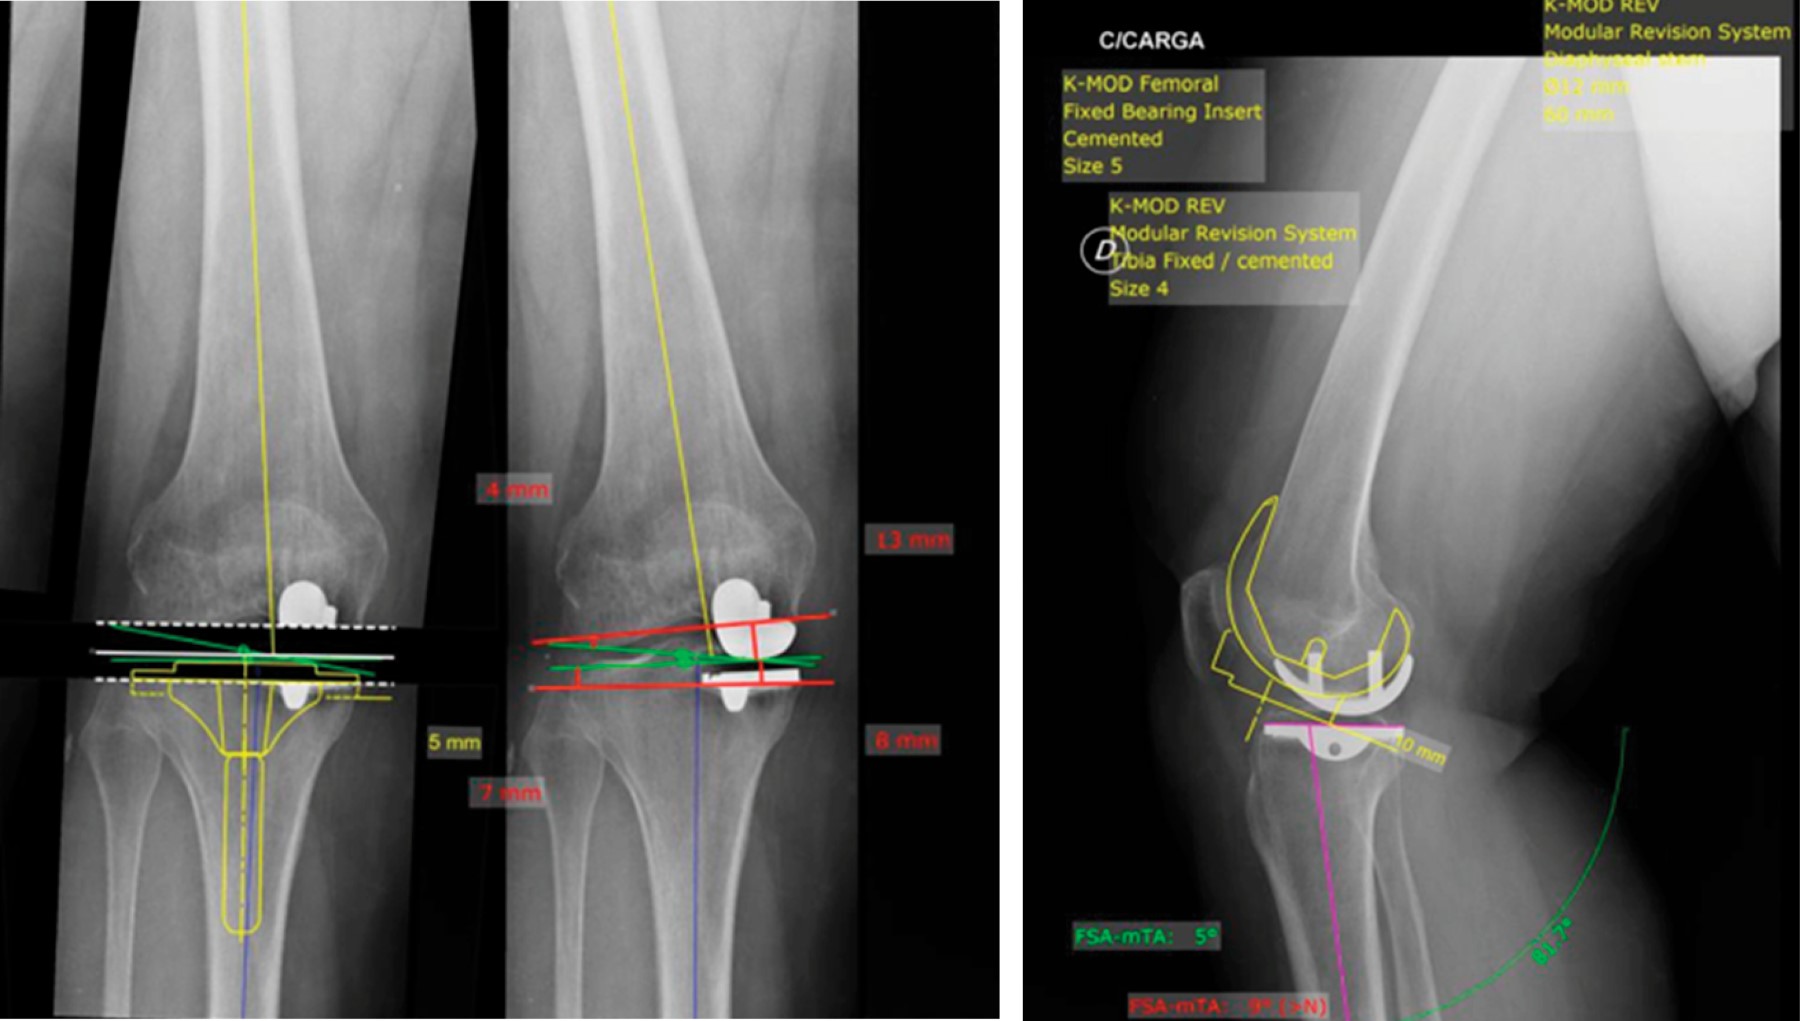

Figure 10

Figure 11

Figure 12

Figure 13